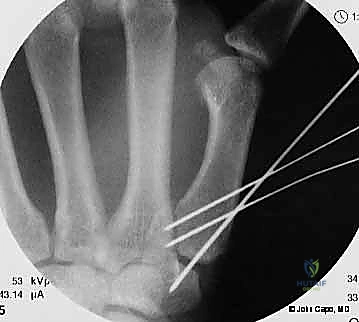

1. الرد المغلق والتثبيت عبر الجلد بالإبر (CRPP - Closed Reduction and Percutaneous Pinning)

هذا الإجراء هو الخيار المفضل لكسور "بينيت" التي يمكن إعادتها لمكانها بدون فتح جراحي كبير.

* الخطوات: يتم إجراء العملية تحت التخدير الموضعي أو الكلي. باستخدام جهاز الأشعة السينية المباشر في غرفة العمليات (C-arm Fluoroscopy)، يقوم البروفيسور هطيف برد الكسر إلى مكانه المثالي.

* بعد ذلك، يتم إدخال إبر معدنية دقيقة (K-wires أو Kirschner wires) عبر الجلد مباشرة لتثبيت قاعدة المشط الأول بالعظم المربعي، وأحياناً بالمشط الثاني لزيادة الاستقرار.

* الميزة: شقوق صغيرة جداً، ألم أقل، وشفاء أسرع. يتم إزالة هذه الإبر عادة في العيادة بعد 4 إلى 6 أسابيع.